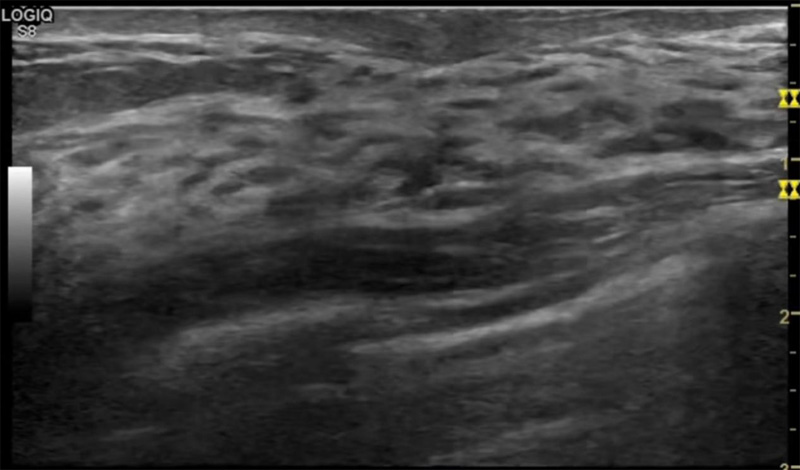

乳房脹痛,觸摸疼痛,手摸起來(lái)感覺(jué)有腫塊。這個(gè)是什么問(wèn)題呢?醫(yī)生診斷一般是乳腺增生。那么在乳腺超聲設(shè)備檢查后,報(bào)告單卻顯示雙乳未見(jiàn)明顯占位性病變。乳腺增生是很多女性,特別是育齡期女性都有的經(jīng)歷、到底乳腺增生癥狀有哪些?會(huì)給我們帶來(lái)怎樣的影響呢?乳腺增生不是腫瘤跟炎癥。乳腺組織增生及退行性變跟內(nèi)分泌功能紊亂有關(guān)系。正常的生理改變。還有乳腺病,良性乳腺結(jié)構(gòu)不良等名稱。

乳腺增生有什么癥狀,病因?比較典型的就是乳房疼痛,特別是經(jīng)前癥狀比較重,經(jīng)后就有所緩解。有時(shí)候還能碰到乳房硬塊。根據(jù)經(jīng)期的變化而變化硬度大小都有變。乳腺在內(nèi)分泌激素,伴隨月經(jīng)周期有增生問(wèn)題。內(nèi)分泌激素代謝失衡,雌激素水平增高,出現(xiàn)乳腺組織增生過(guò)度,增生組織不退的情況下,就會(huì)有乳腺增生癥狀。這個(gè)不會(huì)增加乳腺癌的風(fēng)險(xiǎn)。所以不用緊張的。不過(guò)乳腺癌的病人都會(huì)有乳腺增生。所以乳腺增長(zhǎng)有沒(méi)癥狀,都需要進(jìn)行常規(guī)的體檢。